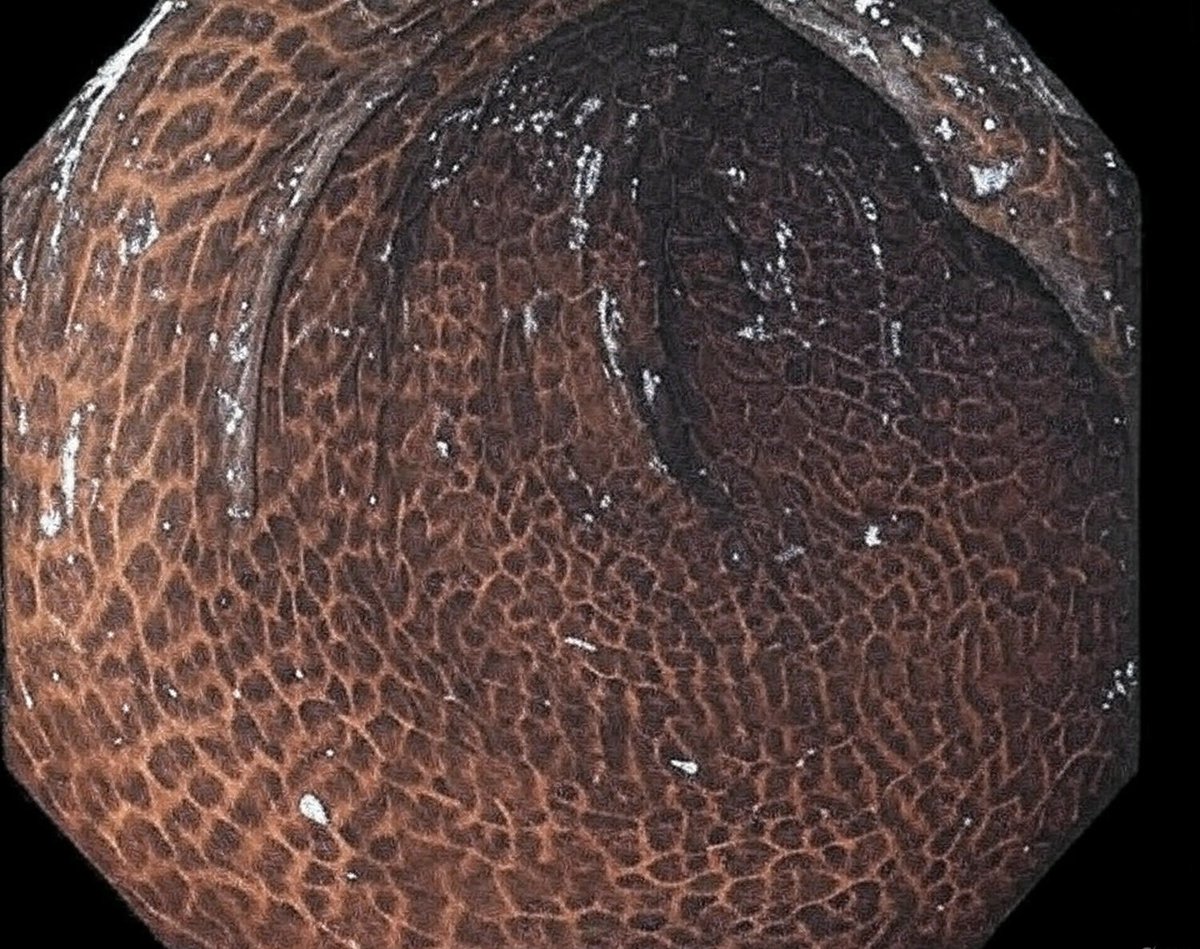

Keith Siau This is melanosis coli due to anthraquinone-based laxative use. Come take a tour 👇🏻 x.com/schowardjd/sta…